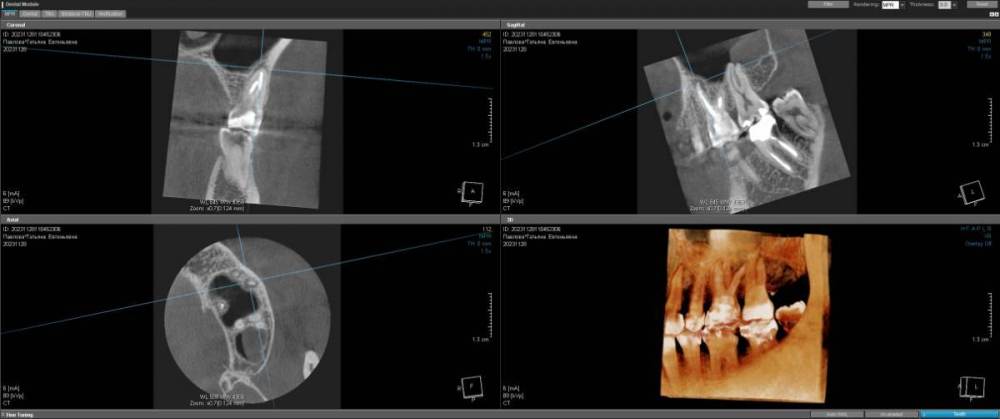

Laniakea Опубликовано 23 февраля, 2024 Поделиться Опубликовано 23 февраля, 2024 (изменено) Здравствуйте! 2 года болит зуб при нажатии после пломбировки каналов (26) 2 раза перелечивали под микроскопом, никто ничего не видит. Ни трещин, ни перфораций, ни осколков. Болит немного при накусывании и очень сильно при постукивании сбоку. Если сжать зубы сильная колюще-режущая боль. Может ли там быть непройденный канал? (найдено 4) 742603586_KLKT55PavlovaTE281123.zip Изменено 23 февраля, 2024 пользователем Laniakea 1 Ссылка на комментарий

Бардо Опубликовано 26 февраля, 2024 Поделиться Опубликовано 26 февраля, 2024 на переднем щечном корне есть воспалительный процесс, лечение проведено адекватное, я бы здесь рассмотрел апикальную хирургию, если вы решите сохранять зуб. Альтернатива - перелечивание с очень сомнительным прогнозом или удаление с имплатацией. Ссылка на комментарий